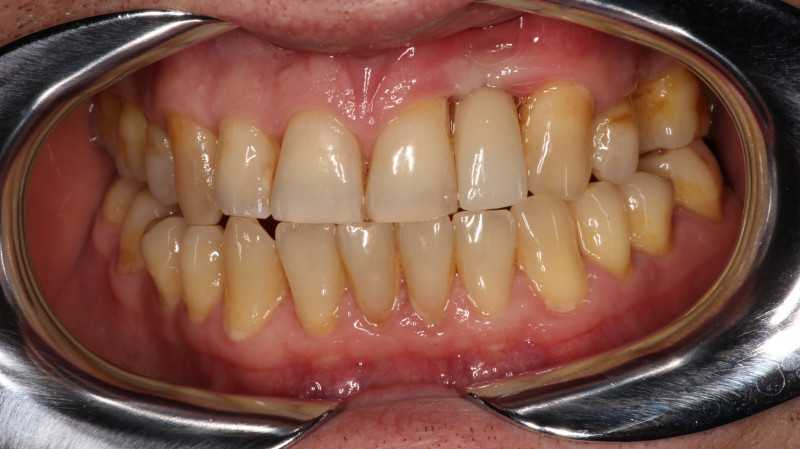

На странице представлено портфолио стоматологий Новосибирска с фото работ до и после имплантации зубов. Мы собрали разные клинические случаи: одиночные импланты, восстановление нескольких зубов и полная реконструкция зубного ряда. Здесь вы можете видеть, как выглядят восстановленные зубы, меняется форма улыбки после процедуры. Изучите результаты до и после имплантации зубов, чтобы оценить качество работы врачей и выбрать стоматологию в Новосибирске, которая поможет вернуть функциональность и эстетику вашей улыбке.

Жалобы: на отсутствие зубов, неудовлетворительную эстетику зубных рядов, невозможность жевать, подвижность зубов. Что сделано: удаление зубов на в/ч и н/ч, установка имплантатов Bredent Sky (верхняя челюсть 6 импл, нижняя 4 импл) и одномоментное протезирование акриловыми протезами с опорой на имплантаты по протоколу Fast & Fixed (зубы за один день). Через 10 месяцев проведена работа по замене протезов на постоянные металлокерамические. Что получил пациент: красивую улыбку, возможность нормально питаться с первого дня после операции.

Жалобы: на отсутствие зубов, неудовлетворительную эстетику зубных рядов, невозможность жевать, снижение высоты прикуса. Что сделано: удаление зубов на в/ч и н/ч, установка имплантатов Bredent Sky и одномоментное протезирование акриловыми протезами с опорой на имплантаты по протоколу Fast & Fixed (зубы за один день). Через 8 месяцев проведена работа по замене протезов на постоянные металлокерамические. Что получил пациент: красивые и ровные зубные ряды, возможность нормально питаться с первого дня после операции, поднята высота прикуса, теперь не стесняется улыбаться.